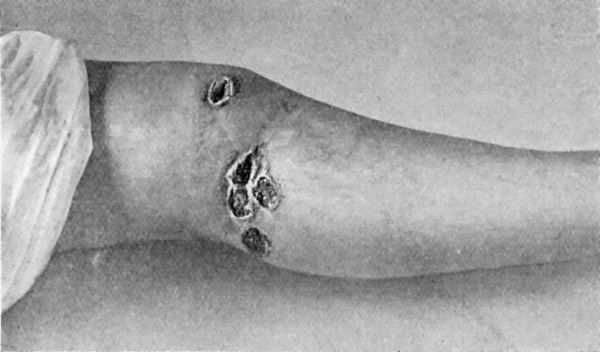

38.Primary Lesion on Thumb, with Secondary Eruption on Forearm 154

39.Syphilitic Rupia 159

59.Dermoid Cyst of Ovary 213

60.Carpal Ganglion in a woman æt. 25 215